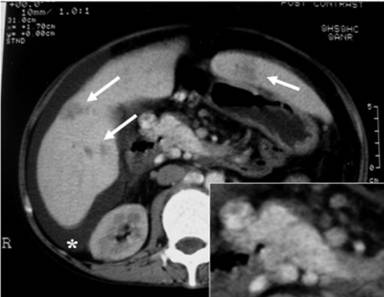

The most commonly affected part of the pancreas was the body region (100%; Figure 1), followed by the head (75%; Figure 2) and tail (50%; Figure 3). The involvement was typically multi-focal (75%; Figures 1 and 2) and in the form of micro-abscesses. Only one patient (25%) had a large focal solitary abscess (Figure 1), affecting the body of the pancreas. Other associated pancreatic findings included splenic vein thrombosis (Figure 2), peripancreatic inflammations and peri-pancreatic fat streaking. Extra-pancreatic manifestations included blood (4 patients), liver abscesses (3 patients; multiple micro-abscesses (Figures 3 and 4) or large ‘honeycomb’-like abscesses), ascites (2 patients; Figures 3 and 4), splenic abscesses (2 patients; Figures 2 and 4) (which also has the ‘honeycomb’ appearance), psoas abscesses (2 patients) and lung (1 patient).

Figure 3. Axial computed tomography image showing multiple pancreatic micro-abscesses visualized in the pancreatic head in association with ascites (asterisk) and multiple hepatic abscesses (arrows) in both lobes. This patient also had micro-abscesses in the body and tail region (Case #3). Insert show a magnified view of the image showing the micro-abscesses. |